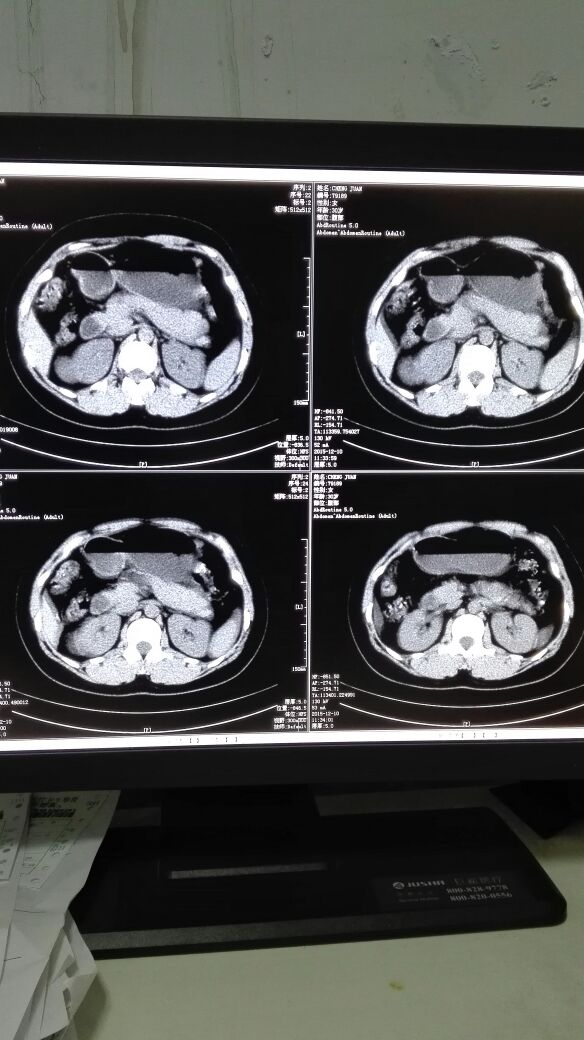

患者女,40岁,医院职工家属。B超体检时发现肝肾间多发囊性占位性病变。行腹部平扫示:右肾上腺区囊性占位,有分割和钙化点,右肾受压下移。诊断意见:右肾上腺囊腺瘤可能性大,建议进一步检查明确。后到市级医院检查并切除手术,病理切片考虑肾上腺囊肿。今腰部不适复查CT片。